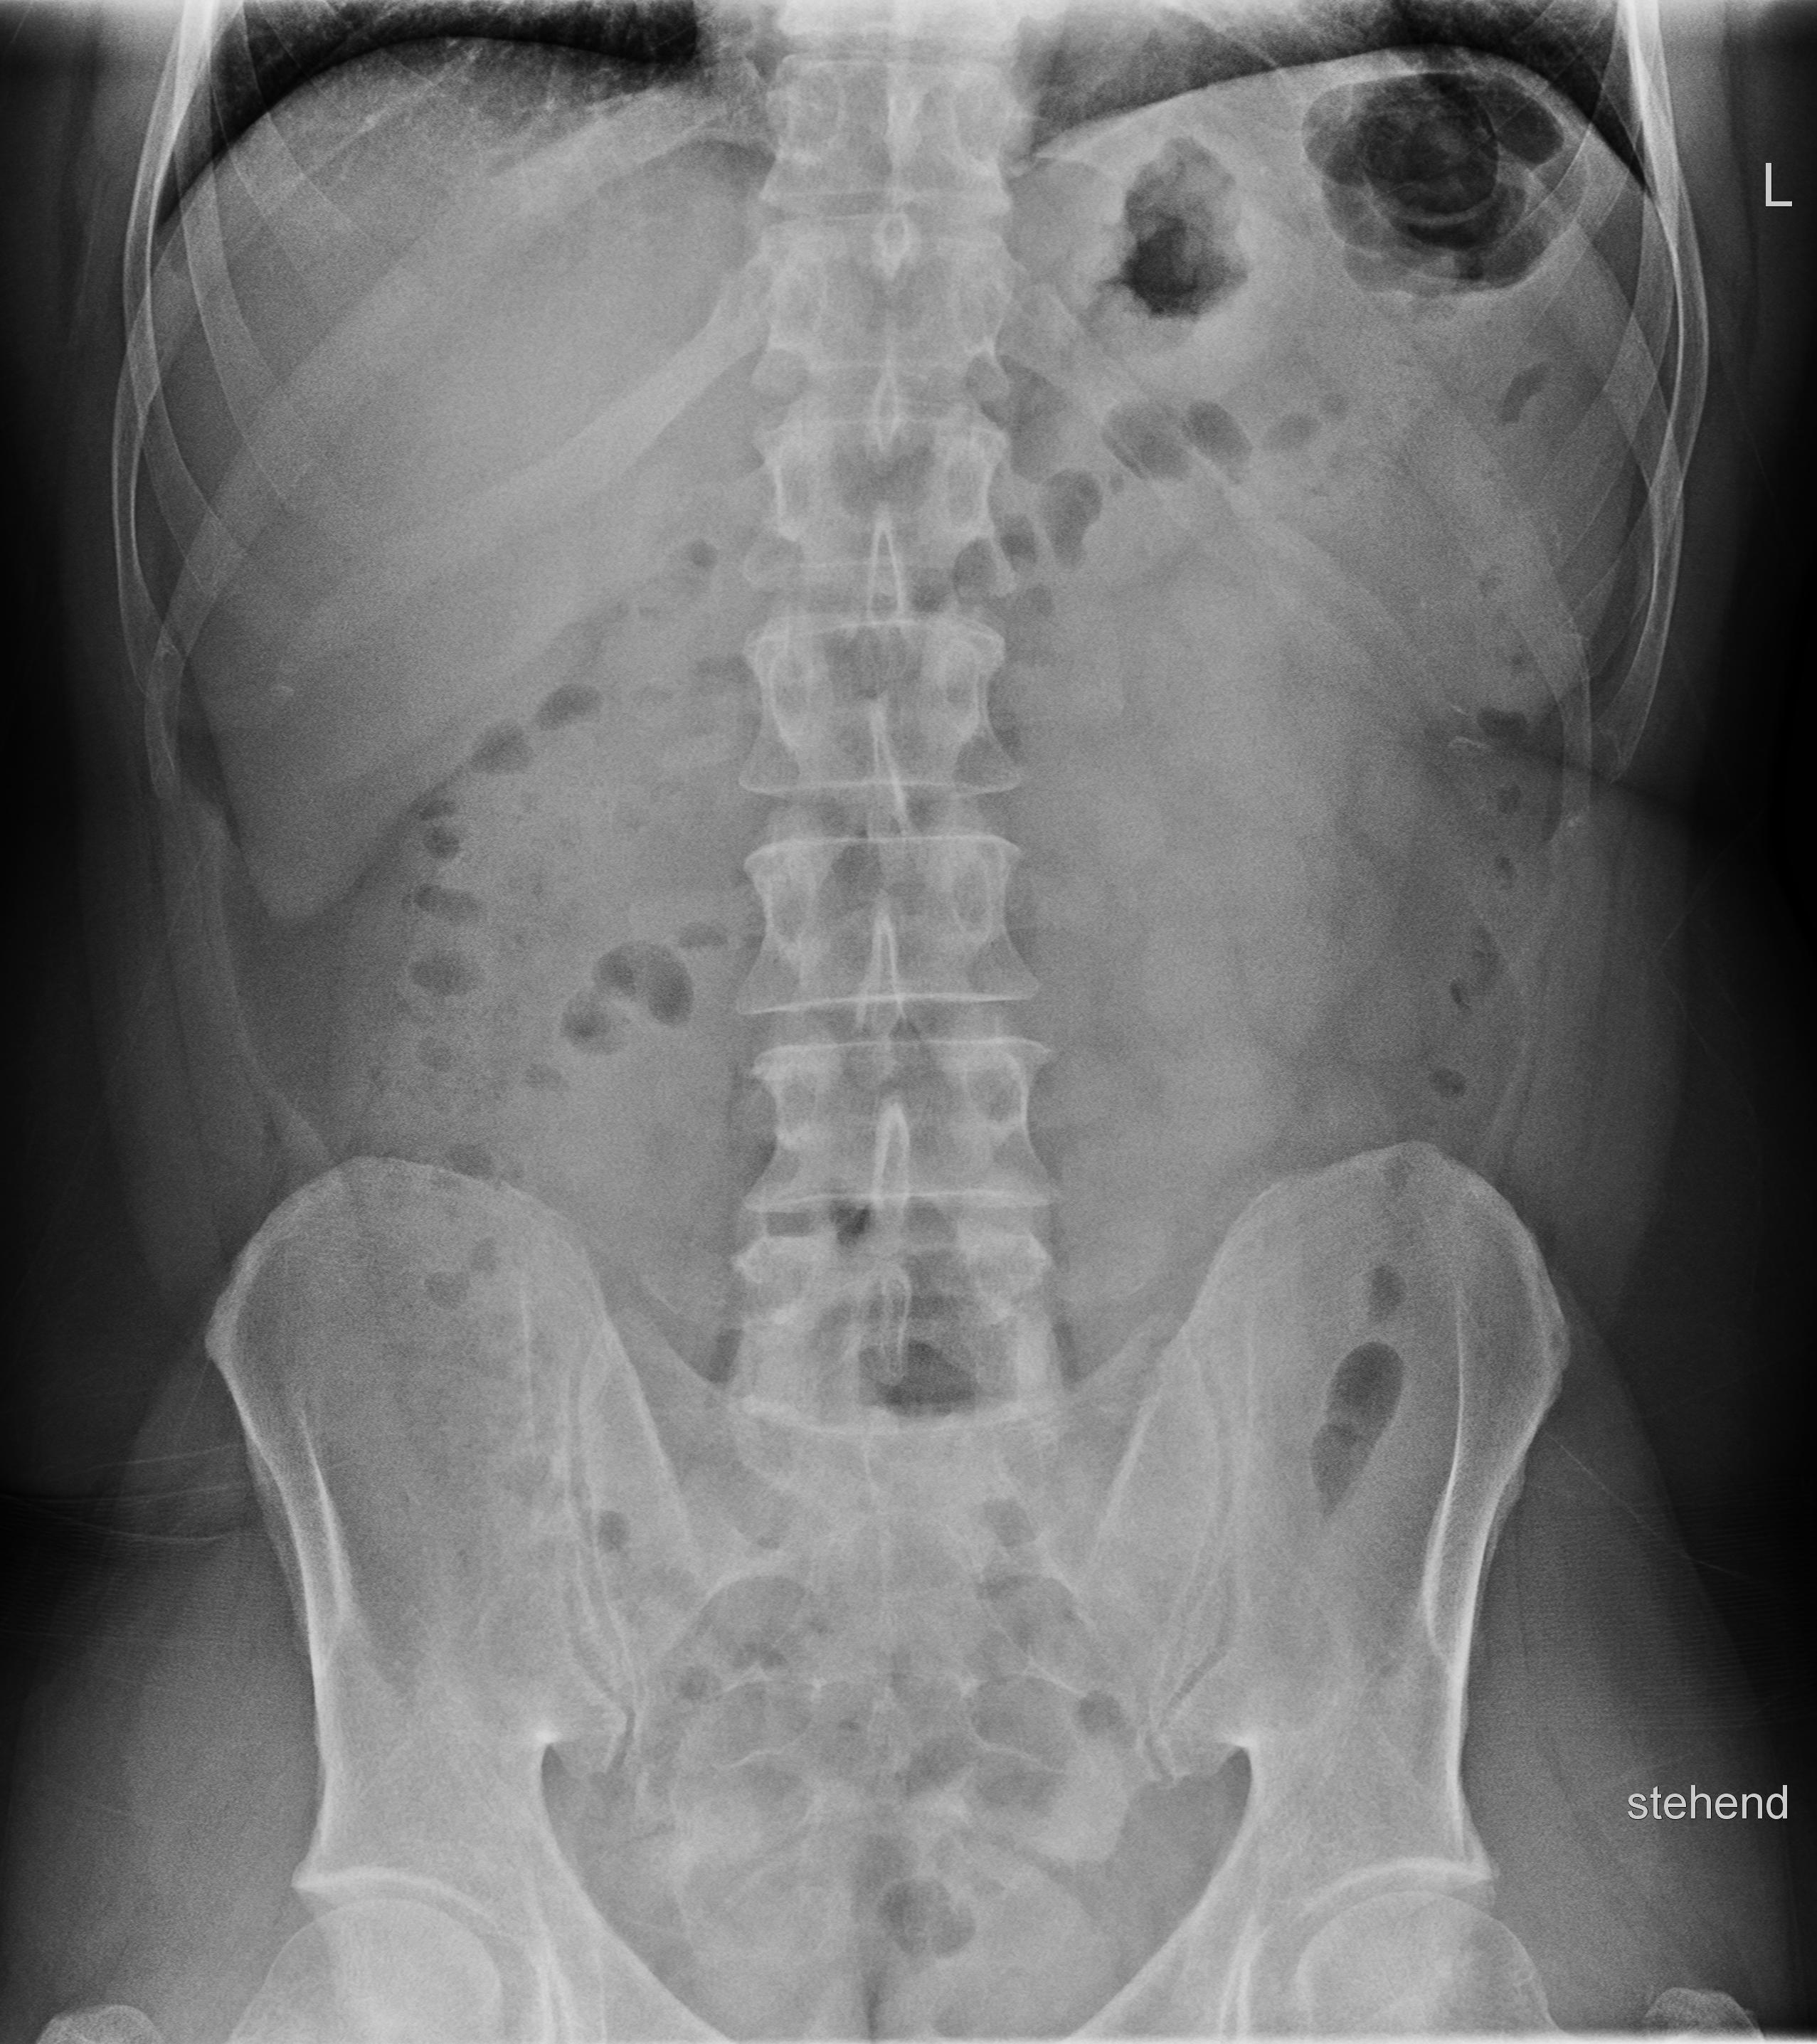

Abdomen p.-a.

freie Luft; Ileus, röntgendichte Fremdkörper

Qualitätskriterien

Die Zwerchfellkuppen sollen gut abgrenzbar sein. Konturen von Leber, Nieren und Psoas sowie seitlich die Bauchwand sollen erkennbar sein.